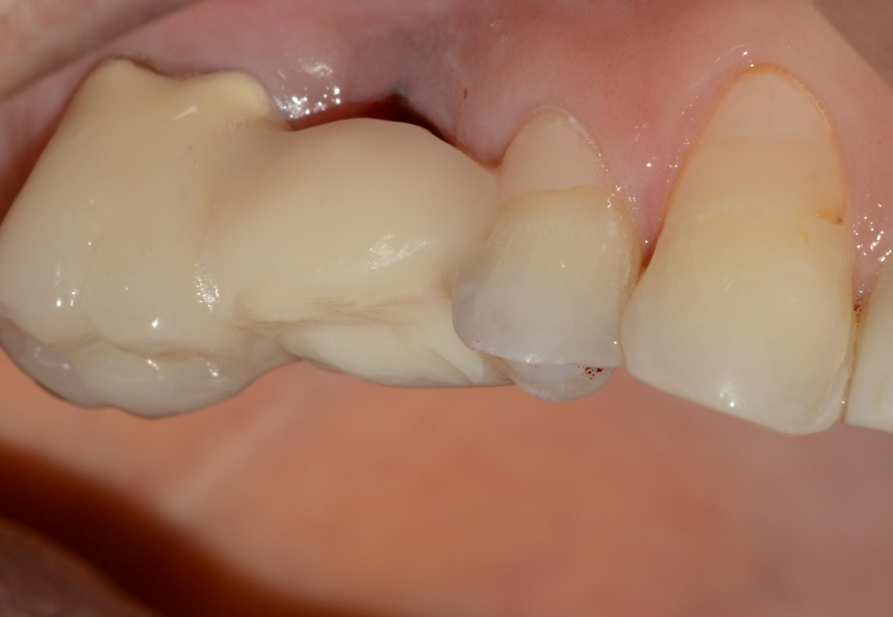

Aguardado o tempo, foi realizada a reabertura do implante com incisão deslocada para a palatal, deixando mais mucosa ceratinizada por vestibular (Figura 12). Foi instalado um Pilar Ideale (Figura 13) e confeccionado um provisório parafusado sobre ele. As suturas acomodaram a mucosa sobre o provisório, conformando-a ao perfil de emergência desejado (Figura 14).

Após 21 dias, a mucosa se apresentava saudável e com um perfil de emergência adequado para a confecção da coroa protética definitiva sobre implante (Figura 15). Foram realizados os procedimentos de moldagem com personalização do transferente para a cópia fiel do perfil de emergência, e uma coroa metalocerâmica foi instalada sobre o Pilar Ideale e a reabilitação foi finalizada (Figura 16).